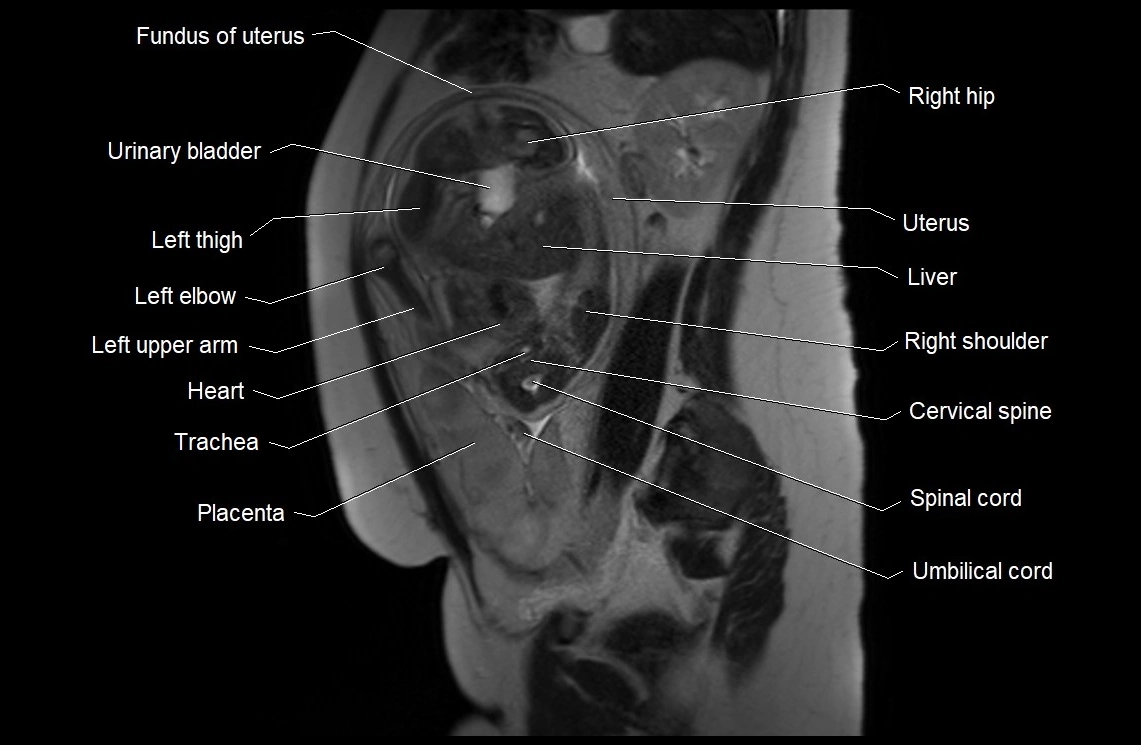

• Imaging relevance: MRI used for fetal visualization and assessing oligohydramnios/polyhydramnios when ultrasound is inconclusive

MRI Appearance

T2 HASTE (T2 GRE):

• Amniotic fluid shows very bright hyperintense signal

• Provides natural contrast against fetus and placenta

• Small particles (vernix) may appear as scattered hypointense foci within bright fluid